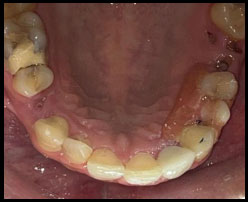

Peeso reamers (sizes 1 and 2) were used for post-space preparation, making sure that 3–4 mm of gutta-percha was retained at the apex. Next, a dual-cure resin cement was used to lute a prefabricated fiber-reinforced post into the canal (Fig. 3). Once the fiber post was in position (Fig. 4). Composite resin was then used to build up the core (Fig. 5). Occlusal view of the core build-up is shown in Fig. (6). Finally, a highly translucent all-ceramic crown was placed, restoring the tooth’s function and aesthetics in alignment with the surrounding dentition in occlusion (Fig. 7) and Occlusal view (Fig. 8).

Core build up- occlusal view.